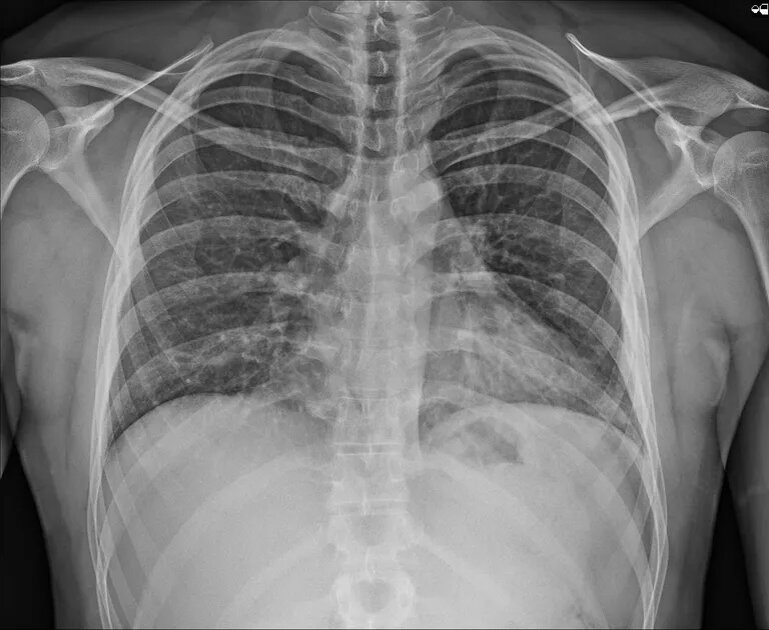

Грудная клетка находится в непосредственной близости от легких, и любое действие по восстановлению целостности ребра может быть высокорискованно. Из-за этого большинство пациентов лечат консервативно, без хирургического вмешательства, что, конечно, замедляет процесс восстановления.